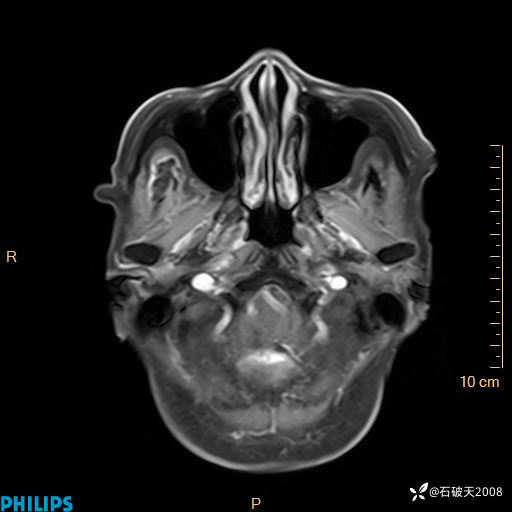

书上说这个肿瘤发生在幕下仅4.09%,你会想到它吗?(病理已公布)

女 86岁 主 诉:乏力1月

现病史:患者1月前活动出现双下肢乏力,无头晕、头痛、恶心、呕吐、肢体活动不利,休息后缓解,间断断发作,症状进行性加重,在家口服药物治疗(具体不详),效差,为进一步诊治,来我院,门诊按“乏力”收住我科,患者自发病以来,神志清,精神稍差,饮食睡眠欠佳,大小便正常,体重未见明显改变。

T2